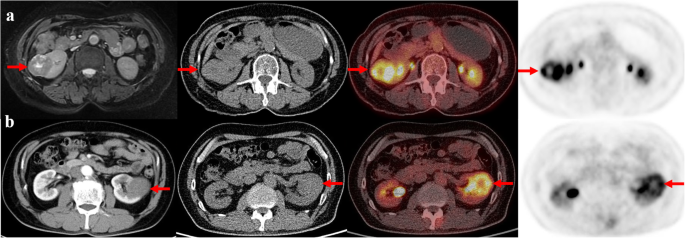

Primary staging scans were performed in 38 patients (Table 1). Thirty-one patients showed FDG-positive renal lesions on PET/CT, resulting a sensitivity of 81.5% (31/38) (Fig. 1). The SUVmax of primary renal lesions ranged from 1.2 to 24.1 (median, 4.8; mean, 6.88 ± 5.27). The SUVmax of high-grade (G3 and G4) papillary RCCs were significantly higher than that of low-grade (G1 and G2) tumors (9.44 ± 6.18 vs 4.83 ± 3.19, P = 0.008). While the SUVmax was not significantly different between type 1 and type 2 papillary RCCs (5.71 ± 2.88 vs. 6.99 ± 5.57, P = 0.563) (Fig. 2). The size of primary renal lesions ranged from 0.9 to 15.6 cm (median, 4.0 cm; mean, 5.04 ± 3.45).

Representative cases. a The axial images from left-to-right are MR, coregistered CT, PET/CT fusion and PET. A 63-year-old woman with type 2 papillary renal cell carcinoma (WHO G3) in the right kidney (arrows). The primary tumor size is 4.4 cm, and the tumor SUVmax is 10.4. b The axial images from left-to-right are diagnostic contrast-enhanced CT, coregistered CT, PET/CT fusion and PET. A 61-year-old man with type 1 papillary renal cell carcinoma (WHO G2) in the left kidney (arrows). The primary tumor size is 4.2 cm, and the tumor SUVmax is 6